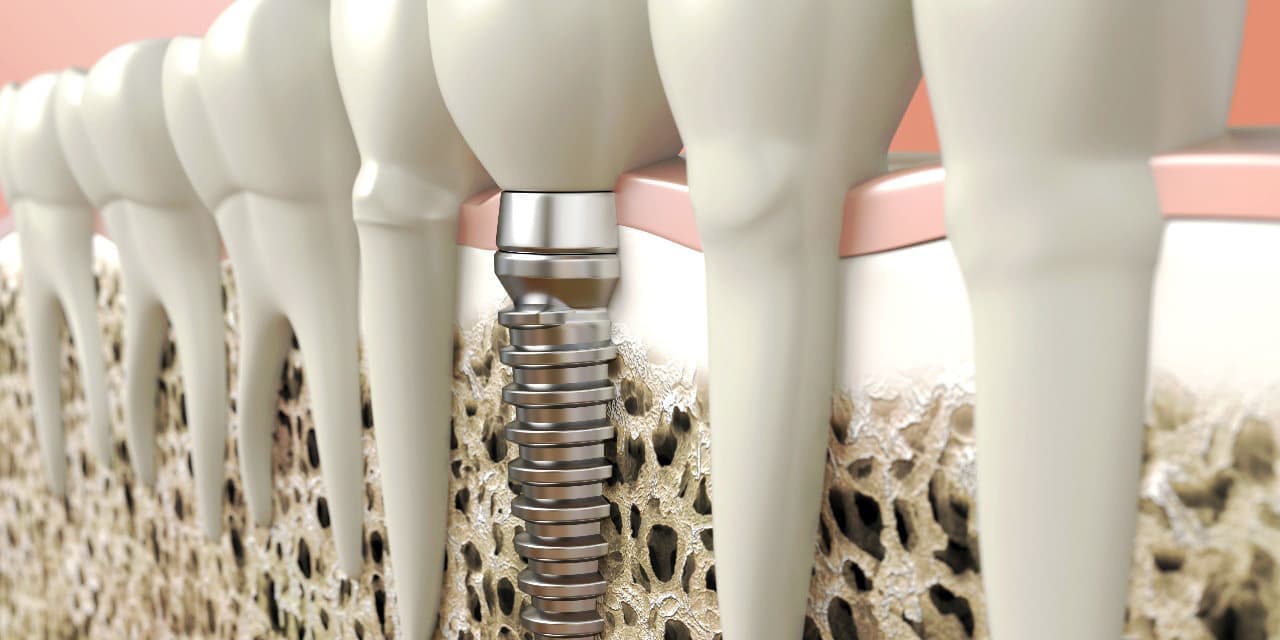

インプラントとは、顎の骨に人工歯根となる金属を埋め込み、それを土台にして、天然の歯と同じような人工の歯を取り付ける治療方法です。

埋め込む金属に生体との親和性が高いチタンが使われる事が多く、チタンは長年の臨床研究でインプラントの素材として最も安全であり、また顎の骨としっかり結合することが確認されています。